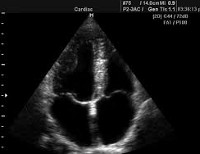

Ultrasound of the heart.

Ультразвуковые исследования сердца. Методы сканирования тканей сердца с использованием высокочастотных ультразвуковых волн. Ультразвуковые исследования в кардиологии включают эхокардиографию (Эхо-КГ) и ее модификации - стресс-эхо-КГ, чреспищеводную эхокардиографию. Эхо-КГ направлено на визуализацию и получение количественных характеристик структур сердца: полостей, стенок, клапанов, магистральных сосудов, мембран сердца. Стресс-эхо-КГ позволяет оценить изменения работы сердца при физическом или фармакологическом стрессе. При чреспищеводной эхокардиографии ультразвуковой датчик, вставленный в пищевод, обеспечивает прямой контакт с сердцем, прилегающим к стенке пищевода.

УЗИ сердца основано на принципе записи ультразвуковых сигналов, отраженных от структур работающего сердца, в режиме реального времени. УЗИ сердца позволяет точно изучить морфологию и механическую активность организма, а также диагностировать структурные и функциональные нарушения. С помощью УЗИ сердца определяется размер полости сердца, толщина и характер движения стенок, функционирование клапанов, параметры кровотока и гемодинамика в сердце. Ультразвуковое исследование сердца, чреспищеводная эхокардиография, стресс-эхокардиография, внутрисосудистое ультразвуковое исследование и контрастная эхокардиография используются в кардиологии. Выбор УЗИ сердца зависит от определенных показаний и определяется после консультации с кардиологом. Цена на разные виды ультразвука различна.

Двумерное УЗИ сердца воспроизводит в реальном времени изображение органа вдоль коротких или длинных осей. Двумерная визуализация исследует размер желудочка, толщину стенок желудочка, клапан и подклапанный аппарат, общую и локальную сократимость, а также наличие тромбов в полостях. Сонография сердца в М-режиме дает вам графическое представление о подвижности стенок сердца и крыльев клапана. Допплеровский режим используется для изучения параметров внутрисердечной гемодинамики.